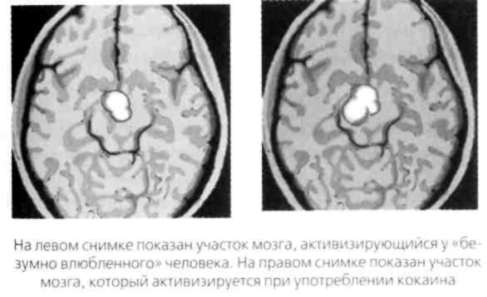

Ниже показаны результаты сканирования мозга «безумновлюбленного» человека и кокаинового наркомана. Убедитесь, что они почтиидентичны.

Итак, влюблены ли вы или просто приняли наркотик, вашиощущения будут одинаковыми. Сканирование также показывает, что у матерей,которые смотрят на своих младенцев, проявляется та же мозговая активность, чтои у людей, глядящих на своих любимых. Бартельс и Зеки сделали вывод о том, чторомантическая и материнская любовь связаны с продолжением рода, поскольку илюбимый человек, и младенец обещают сохранение ДНК.